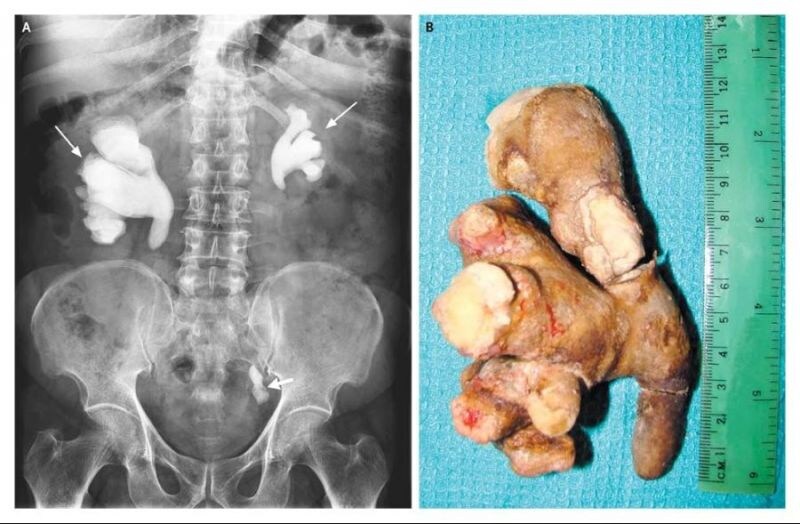

으악.. 뭔 생강을 몸에 넣은거야? 했네..;;;

어우 첫번째 사진 생강인줄알았네

다들 생강 떠오르는건 똑같구나

https://youtu.be/B09nqEm9tqY?si=HblkKMFcJYanwW7E&t=243 극혐 주의 요산이 쌓이다 못해 치즈처럼 썩어서 뼈랑 연골도 다 녹음